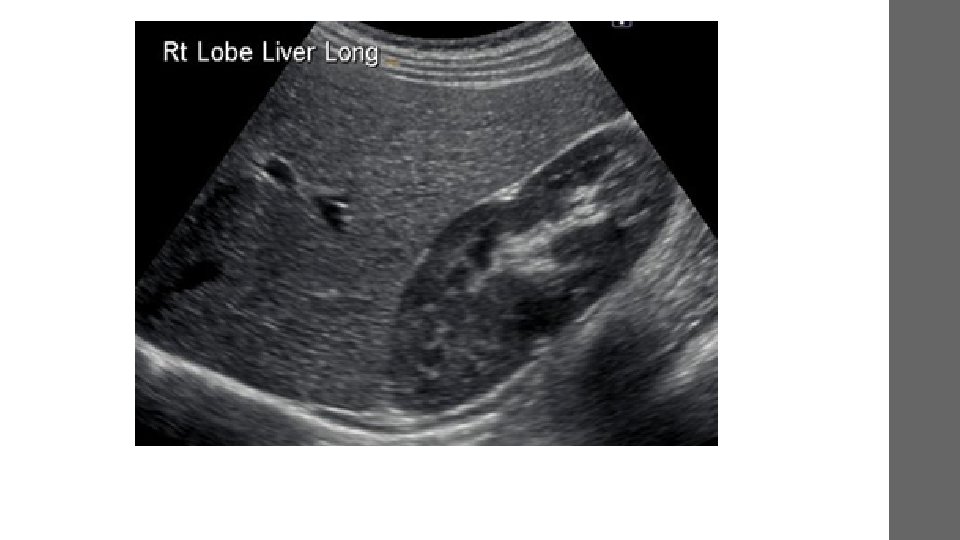

• Can help to diagnose a variety of conditions and to assess organ damage following illness. • Is used to help physicians evaluate symptoms such as: • pain • swelling • infection • hematuria

• heart and blood vessels • Liver • Gallbladder • unborn child (fetus) in pregnant patients • Eyes • Thyroid and parathyroid glands • Scrotum • brain in infants • hips in infants • Spleen • Pancreas • Kidneys • Bladder • Uterus and ovaries,